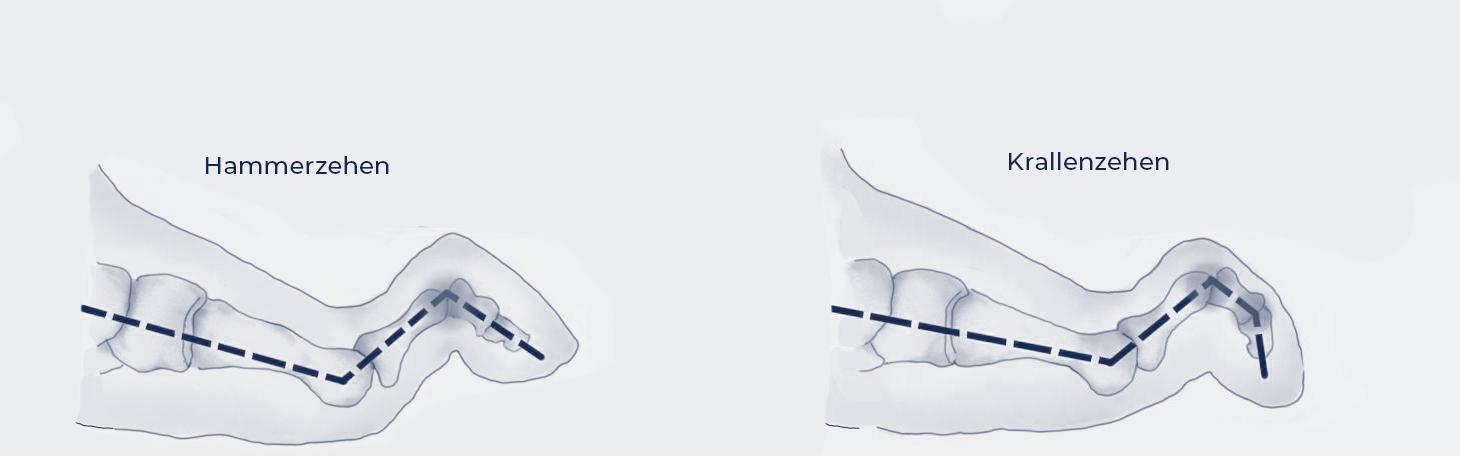

Bildquelle: www.docset.de

Symptome

Hammerzehen zeigen eine Beugung im Mittelgelenk, während Krallenzehen zusätzlich im Endgelenk gebeugt sind. Dies führt zu Druckstellen auf dem Zehenrücken, an der Zehenspitze und unter dem Mittelfußköpfchen. Schmerzen beim Tragen von Schuhen sind typisch.

Ursachen

Häufig sind falsches Schuhwerk (zu eng, zu kurz), Spreizfüße, muskuläre Ungleichgewichte oder neurologische Erkrankungen verantwortlich. Auch eine genetische Veranlagung kann eine Rolle spielen.

Konservative Therapie

Bequeme Schuhe mit ausreichend Zehenfreiheit, Polsterungen zur Druckentlastung, Zehengymnastik und das Tragen von Schienen können die Beschwerden lindern und das Fortschreiten der Verformung verlangsamen.

Operative Therapie

Wenn die konservativen Maßnahmen nicht ausreichen, kann eine Operation in Erwägung gezogen werden. Dabei werden Sehnen verlängert oder versetzt, Gelenke versteift oder Knochen korrigiert, um die Zehen zu begradigen und die Schmerzen zu beseitigen. Auch hier wird, falls möglich, die Operation minimalinvasiv durchgeführt.